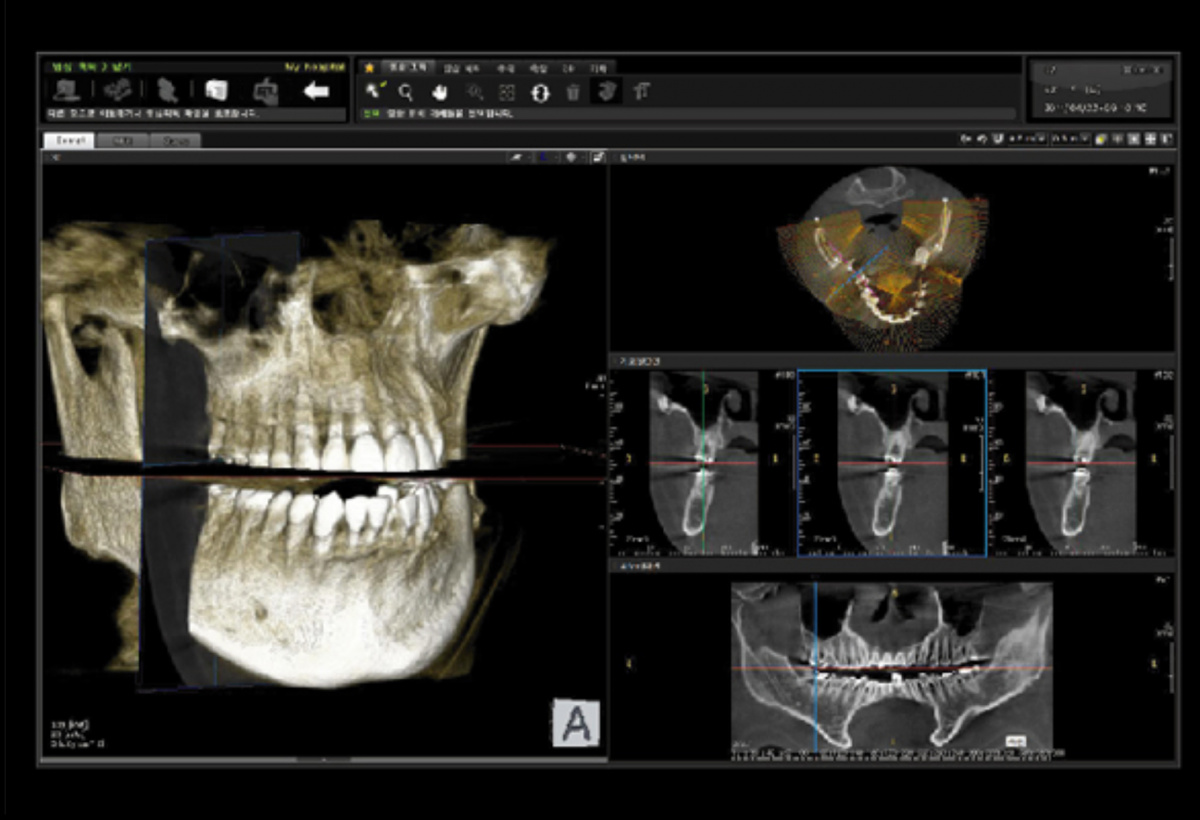

Немаловажным, а может главным вопросом, является универсальность программы-просмотровщика, в которой будут работать врачи-стоматологи. У Papaya 3D есть два варианта программ: Triana и OnDemand3D. Оба просмотровщика обладают схожим интерфейсом и имеют самые важные опции, а именно:

• режим MPR (многоплоскостная реконструкция). Именно здесь выстраивается интересующий участок челюсти или зуба для анализа.

• панорамный реформат. Возможность постройки классической и сегментарной панорамы позволяет продемонстрировать план лечения пациенту, а также оценить расположение анатомических структур на боковых кросс-секциях.

• модуль дентальной имплантации. Возможность виртуальной установки дентального имплантата с анализом окружающей костной ткани. В библиотеке представлен широкий спектр имплантологических систем с индивидуальной прорисовкой имплантата.

• выделение нижнечелюстного канала позволяет продемонстрировать расположение важного анатомического образования и определить зону безопасности при проведении лечения.

• функции плотности, линейных измерений и угла – необходимы для получения полноценной информации для последующего лечения.

• 3D режим – показывает трехмерную модель челюсти с целью определения аномалий, деформация, а также визуализации виртуальных имплантатов.

Таким образом обе программы являются простыми в пользовании, но обладающими обширным спектром возможностей для диагностики любыми специалистами-стоматологами. В данные программы происходит загрузка классических файлов DICOM 3.0, которые являются общепринятым форматом записи данных пациента. Это важный момент, так как позволяют врачу, имеющему полную версию программы загружать даже сторонние исследования и просматривать их в этих программах. Простота в освоении этих программ позволяет даже специалисту, не работающему раннее с этими программами, быстро адаптироваться и получить качественную информацию. Возможность выгрузки STL-файла дополнительно создает возможность интегрировать данные с цифровым ортопедическим протоколом.